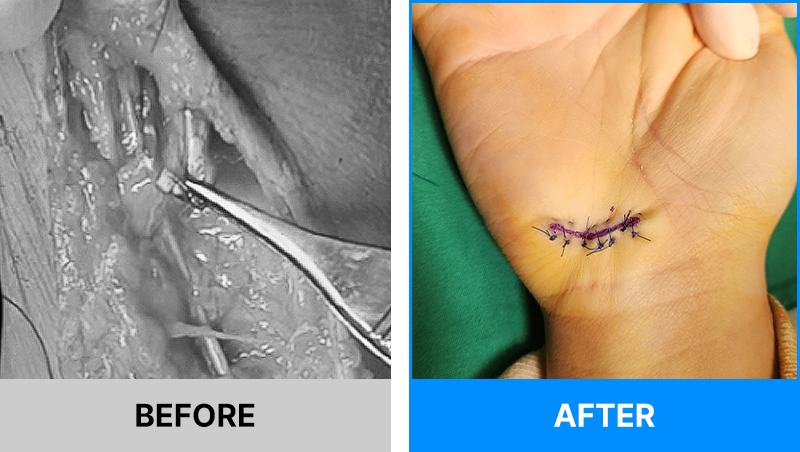

왜 당일 입퇴원 수술일까요?

오래 입원할 필요가 없기 때문입니다.

서울거탑정형외과에서는 전신마취, 척추마취가 아닌

국소부분마취(신경차단) 및 수면 마취를 통해 수술을 시행합니다.

수술 가능 여부 확인은 대표원장과의 진료가 필요합니다.